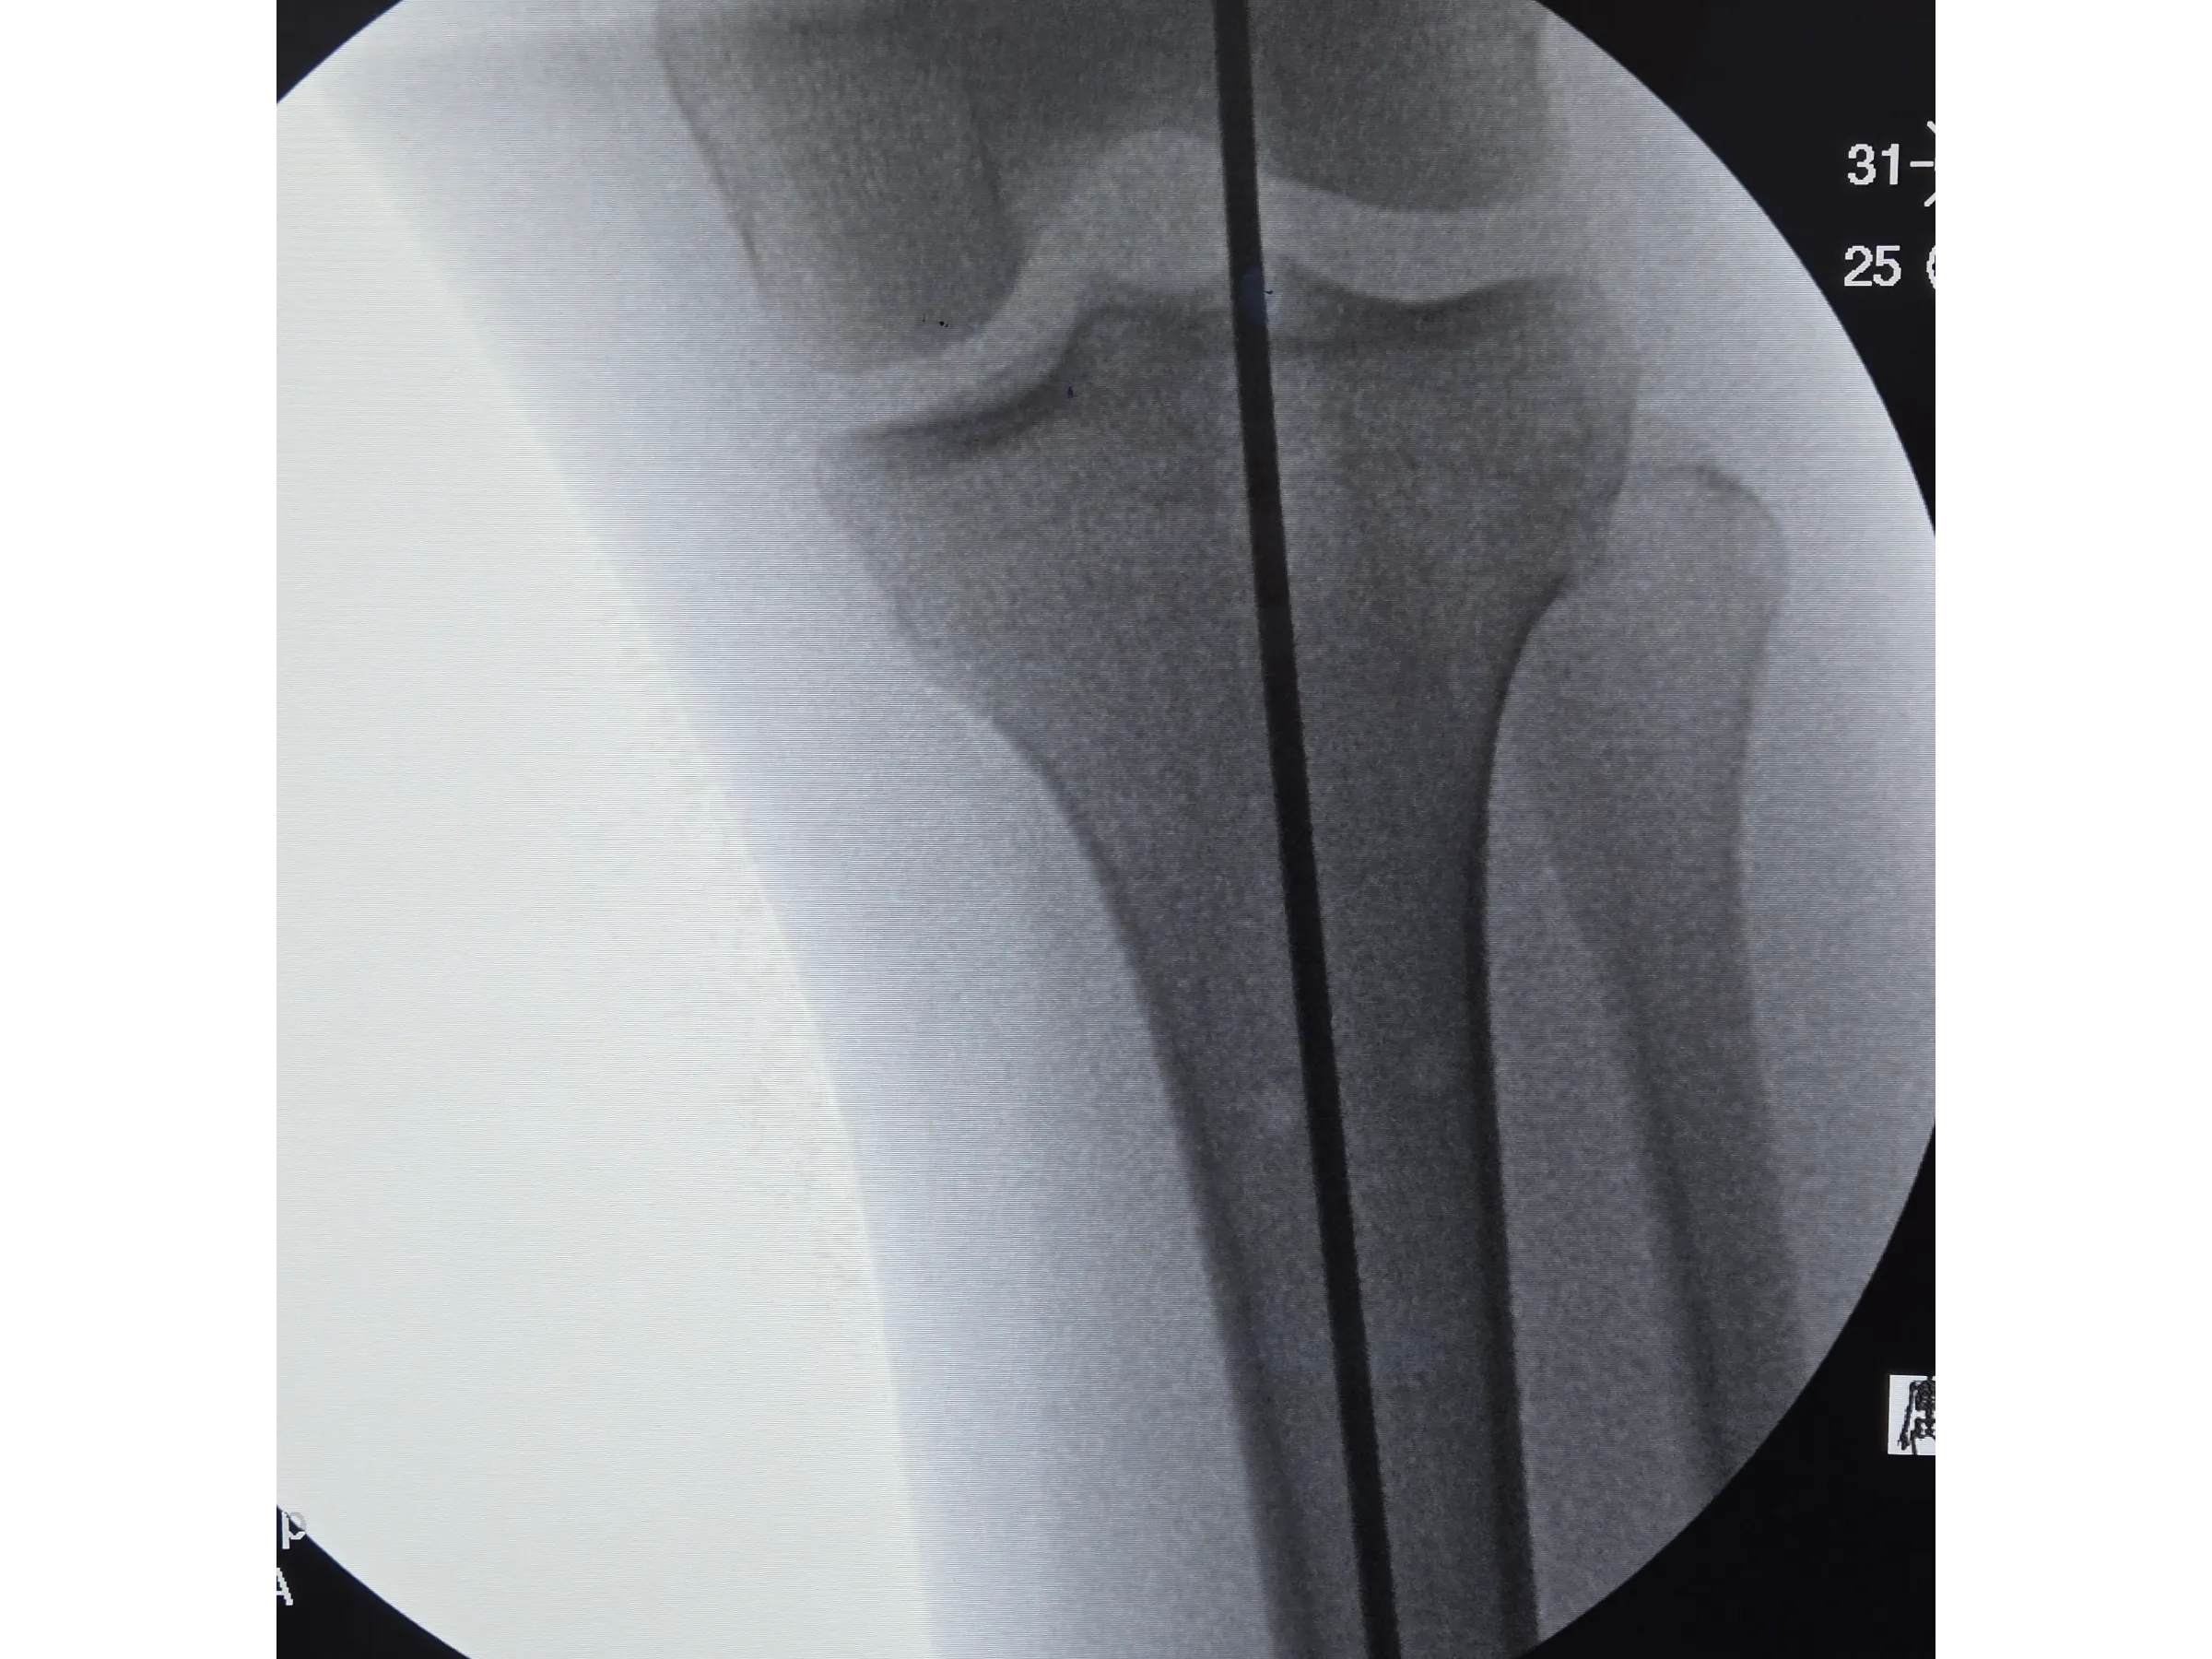

- Introdução segura do fio-guia e fio olivado com controle radiográfico;

- Referência Anatômica Precisa: Técnicas de marcação com caneta dermográfica e fio de Kirschner para garantir alinhamento ântero‑posterior e lateral;

- Controle Radiográfico Eficiente: Métodos para evitar direcionamento posterior do fio-guia e garantir centralização do fio olivado;